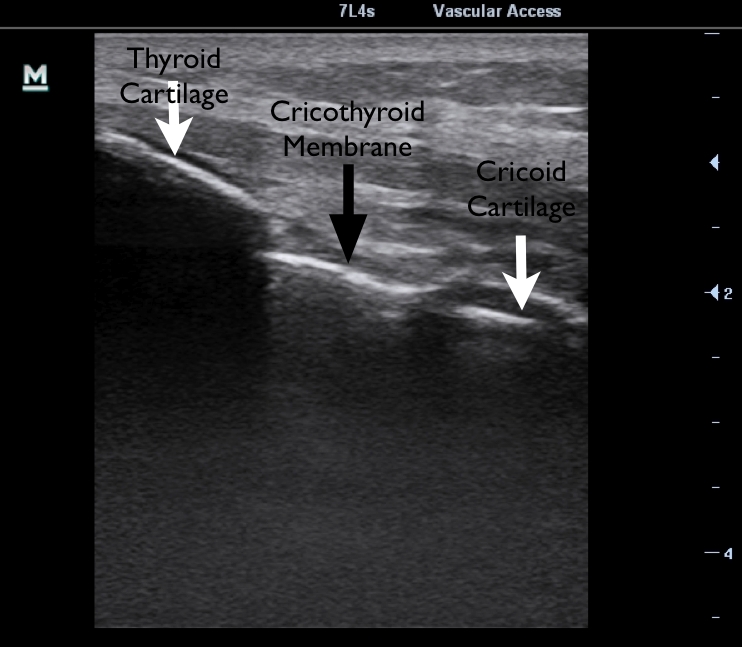

- in the event of ‘can’t intubate, can’t ventilate‘, a surgical cricothyroidotomy should probably be our ‘go-to’ surgical airway of choice. If needle cricothyroidotomy has a failure rate of up to 60% in a hospital setting, it is hard to imagine how it could fare better in the prehospital arena. Of course there may be exceptions to this (difficult neck anatomy etc)